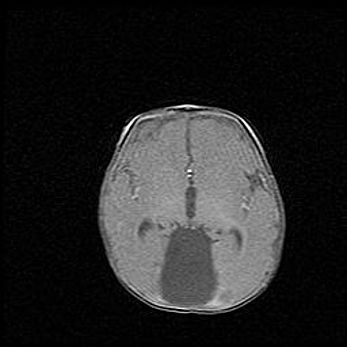

Открытая гидроцефалия.

Возраст: 6 месяцев 15 дней

Вес: 6200 г

Пол: женский

Окружность головы: 41 см

Срок гестации: 38 недель

Гидроцефалия головного мозга у новорожденных – это скопление избыточного количества цереброспинальной жидкости в головном мозге. Ее избыточное скопление в мозге приводит к патологическому расширению желудочков мозга (четырех полостей, расположенных в глубине белого вещества мозга, заполненных цереброспинальной жидкостью и связанных узкими проходами).

Открытый тип гидроцефалии (сообщающаяся) наблюдается тогда, когда нарушен механизм всасывания ликвора в системный кровоток. При этом типе причиной заболевания чаще всего является перенесенные ранее инфекции (например: менингит),  либо же наличие крови в субарахноидальном пространстве.